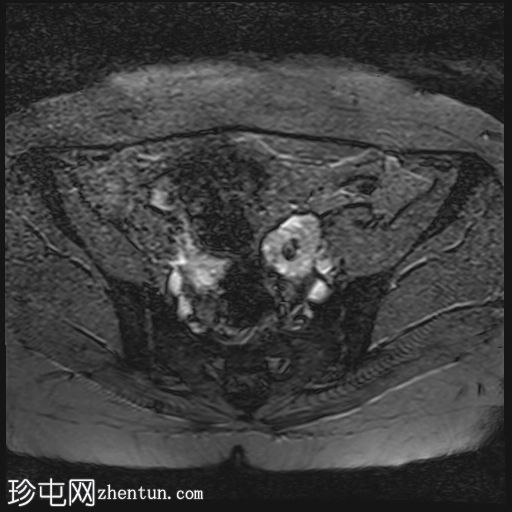

轴位

T2加权像

双侧卵巢位置接近(卵巢相吻),左侧卵巢内可见一边界清晰的囊性病变,大小约3.1 × 2.7 × 2.9 cm,T1加权像呈高信号,T2加权像可见暗点征及内部暗点征。以上MRI特征符合卵巢子宫内膜异位囊肿的诊断。

右侧卵巢可见一囊肿,大小约为 2.8 × 2.0 × 2.2 cm,T1 加权像呈高信号,囊内可见液-液平面,提示囊内含有不同时期的出血性物质。由于对侧卵巢存在典型的子宫内膜异位囊肿,且该囊肿无强化,影像学表现强烈提示为另一子宫内膜异位囊肿。

双侧卵巢均可见多个小卵泡。

双侧卵巢囊性病变,MRI 表现符合子宫内膜异位囊肿的特征,左侧较大。未见强化壁结节或实性成分,提示无恶性转化。